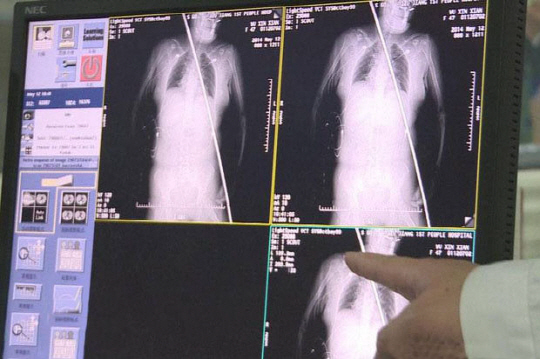

응급실로 옮겨진 그녀를 진찰한 의료진은 "그녀가 병원에 도착했을때 생존 여부를 확신할 수 없었다"며 "하지만 다행히 쇠막대가 동맥 등을 건드리지 않아 큰 출혈이 없었고 주요 장기 또한 멀쩡해 생존할 수 있었던 것으로 보인다"고 말했다.